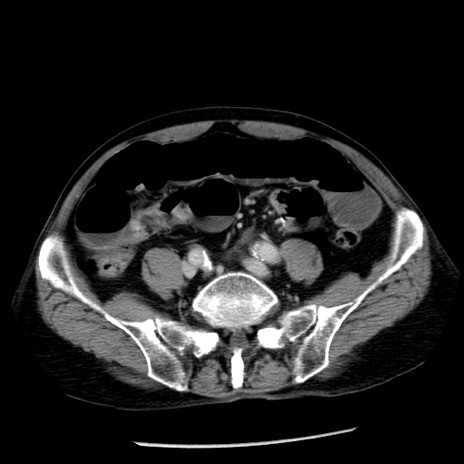

症例26(横断像)

【症例】80歳代男性

【主訴】嘔吐

【現病歴】昨晩2回嘔吐あり、今朝になっても嘔吐あり。来院。

【既往歴】胃潰瘍

【身体所見】意識清明、BT 37.6℃、BP 166/95mmHg、HR 100bpm、SpO2 97%、腹部:平坦・軟、腸蠕動音聴取良好、圧痛なし。

【データ】WBC 21900、CRP 1.46